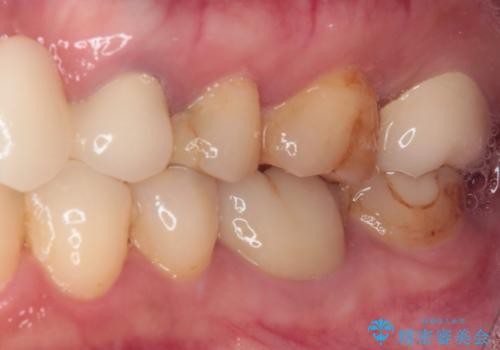

- 他院で矯正治療を終えたものの、むし歯や欠損部の治療が進められないとのことで来院された患者様です。

欠損部や、銀歯やむし歯の大きな歯はセラミッククラウンやブリッジに、小さいむし歯はセラミックインレーにて治療を行うこととしました。

歯肉の状態がとても、短期間でスムーズに治療を終えることができました。